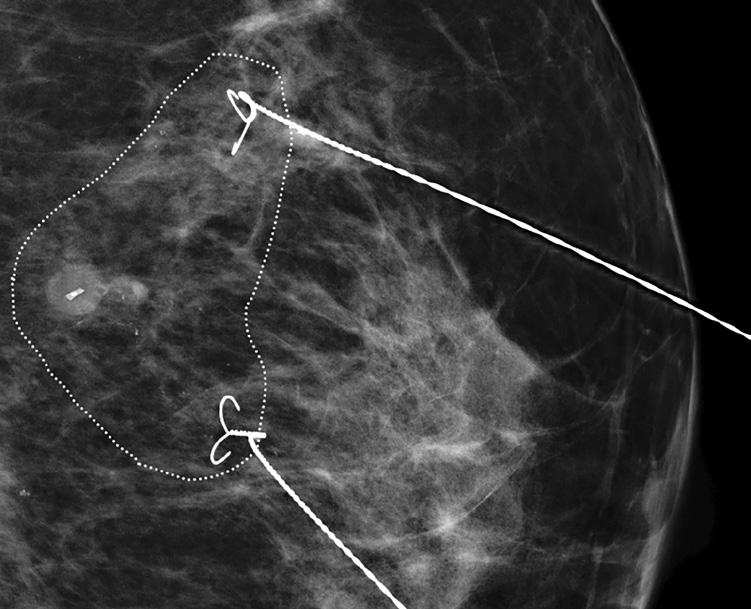

Jodkorn gir en langtidsholdbar markering med høy presisjon, men krever spesifikke prosedyrer for håndtering pre, per- og postoperativt. Dette inkluderer prosedyrer for håndtering av radioaktivt avfall. Radar-markører angir nøyaktig lokalisasjon i brystet, men krever eget utstyr peroperativt og kan gi artefakter på MR. Kull-markering er enkel å implementere og billig. Den kan imidlertid diffundere over tid og gjøre eksakt peroperativ lokalisasjon vanskelig. Titan-klips er en permanent markør som er enkel å plassere, men kan være vanskelig å identifisere ved enkelte bildediagnostiske metoder og krever preoperativ trådmarkering (4). Studier viser at bruk av markører reduserer risikoen for positive kirurgiske marginer og forbedrer presisjonen ved brystbevarende kirurgi (5). (Bilde 1)

1: Mammografi med titanmarkør i tumor og merketråder som viser utbredelse av gjenværende kalk som anbefales eksidert.

EVALUERING AV RESPONS OG KIRURGISK STRATEGI

MR er standard modalitet for evaluering av behandlingsrespons, med sensitivitet på 86-92 % og spesifisitet på 60-89 % (10). Mammografi er viktig ved maligne mikroforkalkninger, da gjenværende DCIS (ductalt carcinoma in situ) kan være til stede selv ved komplett respons på MR (11). Pasientene diskuteres i et eget MDT-møte, der strategi for responstilpasset kirurgi legges. Her vurderes radiologisk og klinisk utredning før og under/etter den neoadjuvante behandlingen. I tillegg planlegges peroperativ merking av gjenværende tumorområde i tilfeller der brystet kan bevares, enten ved hjelp av merketråder (guidewire) mot tidligere innlagte markører eller ved hjelp av prober dersom pasienten har fått jodkorn, radarmarkør eller tilsvarende. En plan for kirurgi i bryst og aksille legges. Endelig beslutning om kirurgisk prosedyre gjøres basert på klinisk undersøkelse, komorbiditet og alltid i samråd med pasienten.